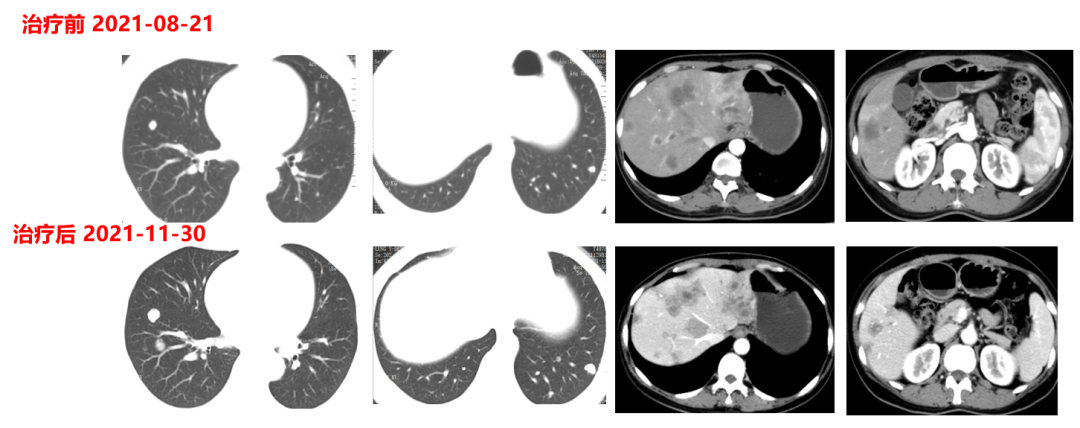

二线治疗(2021-12至2022-8-3,二线PFS:7月余):

于2021-12-03、2021-12-27给予伊尼妥单抗+吡咯替尼方案治疗2周期。2022.1.19始给予患者伊尼妥单抗+吡咯替尼+替雷利珠单抗治疗,两周期,四周期时的疗效评估可以看到,肺上病灶明显缩小,甚至有的病灶消失,肿瘤标志物也在持续下降。

肿瘤第二次进展(2022-8-3):在二线治疗7月余后,肿瘤标志物升高,CT也显示,肺上的病灶增大,患者双靶向+免疫治疗进展。